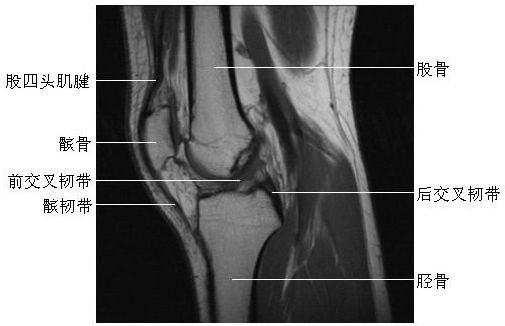

膝关节矢状面(一)

膝关节矢状面(二)

膝关节矢状面(三)

膝关节矢状面(四)

膝关节矢状面(五)